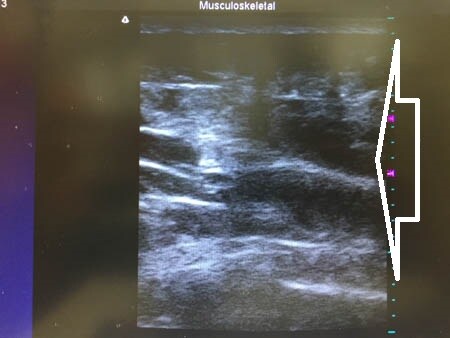

3Dタッチビュー(=超音波)で

皮下脂肪層の変化を見てみましょう。

上腹部。

↓ ↓ ↓

上の画像の部分をつまんでみましょう。